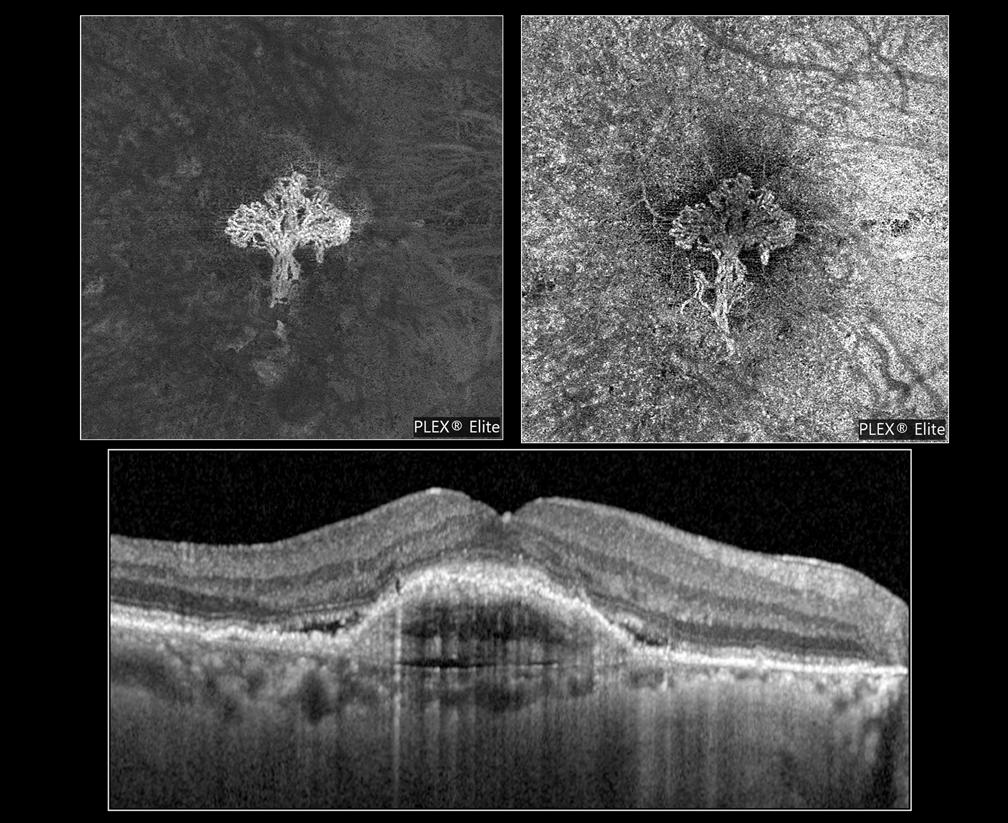

Purtscher Retinopathy in Nonhuman Primate

Purtscher retinopathy is often associated with blunt trauma, but may also occur in other systemic conditions like acute pancreatitis, hemolytic uremic syndrome, and renal failure where acute complementmediated leukoembolization likely contributes to the typ-

ical appearance of cotton-wool spots, retinal hemorrhage, optic disc edema, and inner retinal whitening. Affected patients also experience reduced vision acuity with possibilities of eyesight recovery, depending on the disease progression in other affected organs.1 However, the

a c d e b

Figure 1: Multimodal imaging of NHP Purtscher-like retinopathy. (a) External photographs, (b) color fundus photographs (FP), (c) spectral-domain optical coherence tomography (OCT), (d) early-phase fluorescein angiography (FA), and (e) late-phase FA of the left and right eyes of the affected macaque during the clinical eye examination at 16 years old. Abbreviations: OD, right eye; OS, left eyes. Scale bars, 200µm.

A 16-year-old female rhesus macaque (Macaca mulatta) was diagnosed with severe Purtscher-like retinopathy during a routine eye examination. Intraocular pressures were 7 and 8 mmHg for the right and left eye, respectively, but with no other anterior segment abnormalities (Figure 1a). Fundus examination and photography revealed diffuse cotton-wool spots bilaterally extending across both macula and periphery, which corresponded to the nerve fiber layer (NFL) thickening on optical coherence tomography (OCT) suggesting NFL infarction (Figures 1b and 1c). OCT also showed severe retinal edema with intraretinal and subretinal fluid which was more prominent in the right eye (Figure 1c). Intraretinal hyperreflective foci were also apparent on OCT, suggesting intracellular infiltrates that are likely inflammatory in nature. Early-phase fluorescein angiography (FA) of the right eye showed choroidal filling defects suggestive of

patchy choroidal ischemia while late-phase FA exhibited multiple foci of leakage, suggestive of increased retinal vessel permeability in both eyes (Figures 1d and 1e). The affected macaque died one month after the eye examination. At necropsy, the cause of the sudden death was attributed to left ventricular hypertrophy. Damage to the kidneys and the lungs were found with glomerulosclerosis and interstitial fibrosis in the kidneys along with tubular casts, blood, and high levels of protein found in the urine. Acute pulmonary edema was also noted. Furthermore, the tricavitary fibrinous effusion and focal acute myocardial necrosis suggested that this animal was septic although the source of infection was unknown. We hypothesize that the sepsis and renal failure were the cause of the Purtscher-like retinopathy in nonhuman primates.